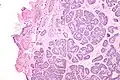

| Micrograph of a Sertoli cell nodule. H&E stain. | |

A Sertoli cell nodule is a benign proliferation of Sertoli cells that arises in association with cryptorchidism (undescended testis).[1] They are not composed of a clonal cell population, i.e. neoplastic; thus, technically, they should not be called an adenoma.[2]

Sertoli cell nodules are unencapsulated nodules that consist of:[2][3][4]

- cells arranged in well-formed tubules (that vaguely resemble immature Sertoli cells), with

- bland hyperchromatic oval/round nuclei that are stratified, and

- may contain eosinophilic (hyaline) blob in lumen (centre).

Micrograph of a Sertoli cell nodule. H&E stain.

Micrograph of a Sertoli cell nodule. H&E stain. -

Micrograph of a Sertoli cell nodule. H&E stain.

Micrograph of a Sertoli cell nodule. H&E stain.